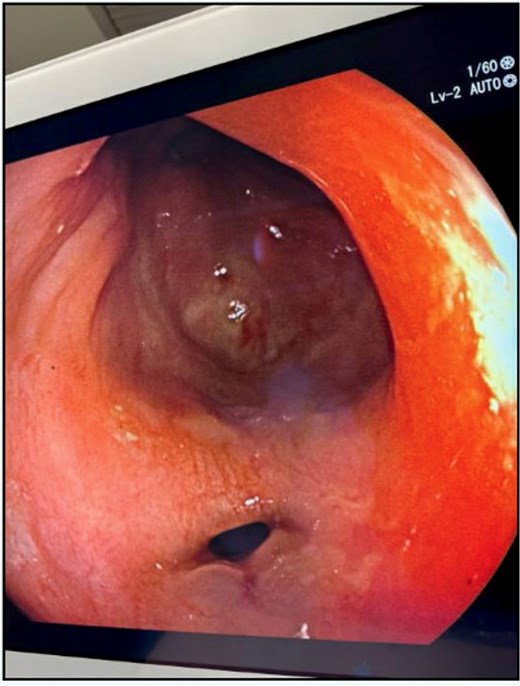

The patient’s leukocytosis resolved during hospitalization, and she was discharged on hospital day 5 with dietary modifications, including a low-fiber diet. At 4-week follow up, flexible sigmoidoscopy demonstrated near-complete healing of the rectal perforation, with only minimal residual mucosal disruption (Fig. 3). By 6 weeks post-injury, follow-up flexible sigmoidoscopy confirmed complete mucosal healing and restoration of normal rectal wall architecture, though mild rectal stenosis persisted (Fig. 4). The patient remained asymptomatic with resolution of her initial symptoms.

Flexible sigmoidoscopy at 6 weeks demonstrating complete mucosal healing and re-epithelialization at the prior perforation site, with no residual defect or inflammation.